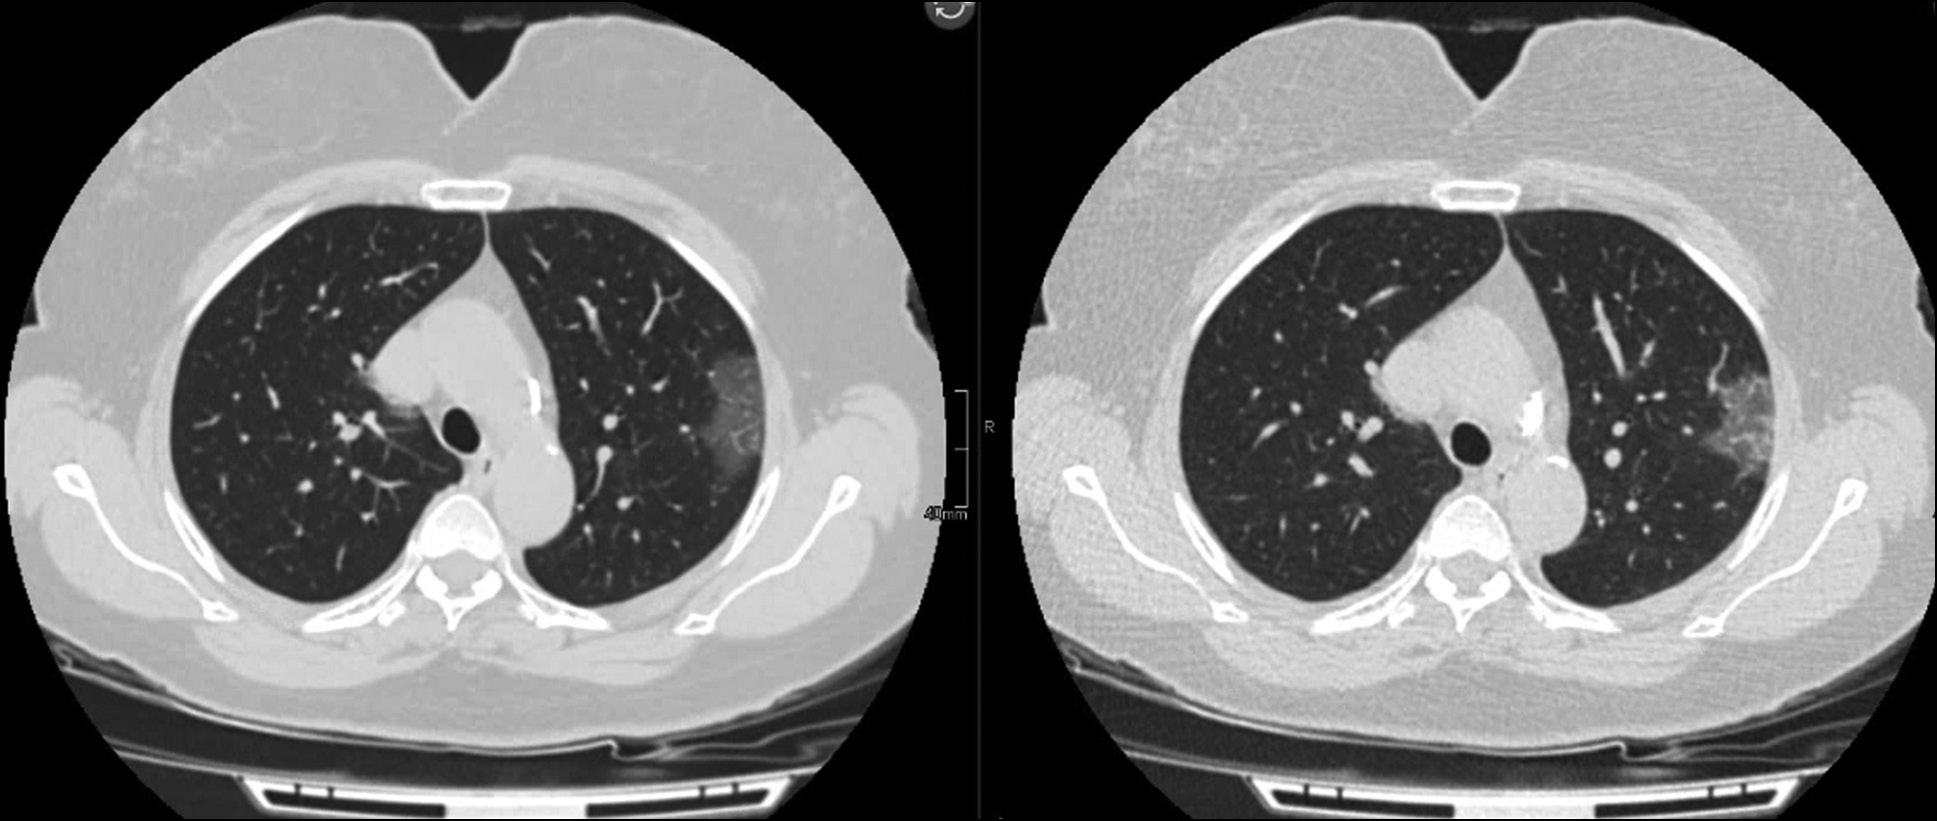

Any special low-dose protocols require clinical validation and comparison with the gold standard. Therefore, clinical trials of the developed LDCT protocol for COVID-19 used standard CT as a reference technique. [28] Some of the clinical images obtained using the developed protocol are shown in Figs. 2 and 3.

Figure 2. Radiation exposure is reduced by 5 times. Patient, 59 y. o., BMI 29 kg/m2. Computed tomography with a soft tissue filter (effective dose: 9.7 mSv), low-dose computed tomography with a soft tissue filter (effective dose: 2.1 mSv). In the upper lobe of the left lung, there was a peripheral ground-glass lesion.

Figure 3. Radiation exposure is reduced by 1.5 times. Patient, 44 y. o., BMI 46 kg/m2. Computed tomography with a soft tissue filter (effective dose: 15.3 mSv), low-dose computed tomography with a soft tissue filter (effective dose: 10.5 mSv). Bilateral peripheral ground-glass lesions.